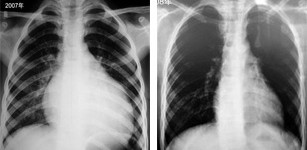

图3 无休止性室性心动过速患者的心电图

无休止性心律失常 定义 指持续发作或反复、顽固性发作的心动过速。当心电图记录的心动过速比例占总数>50%(室上性心动过速)或10%[室性心动过速(室速)]时,可诊断为无休止性心动速(incessant tachycardias),且该疾病易诱发心动过速性心肌病。 发生机制 多为折返机制,如无休止性室速,少数为自律性,如不良性窦性心动过速(窦速),此外还包括触发性机制。以折返机制为例,由于患者既往已具备了折返发生的三要素(双径路、单向阻滞及缓慢传导),因此患者心动过速虽能暂时终止并恢复窦性心律,但下次的窦性心律仍可诱发心动过速(图3)。 分型 ①持续发作:心动过速持续不间断发作,可长达几个月至几十年;②顽固性、反复间歇性发作:心动过速每次发作持续时间不等,停止后可再次发作。 治疗 药物疗效差,射频消融术疗效显著,并能根治该疾病。 心动过速性心肌病 临床研究及动物实验均已证实,长期持续存在频率较快的心动过速,可造成心脏进行性增大及心功能不断下降,并最终导致合并心衰的心肌病。由于心动过速为其病因,故称为心动过速性心肌病。 常见心律失常类型 ①不良性窦性心动过速;②持续性房性心动过速(房速);③慢性心房颤动、心房扑动;④无休止性交界区反复性或自律性心动过速;⑤无休止性室速等。 诊断标准 ①有无休止性心动过速的长期病史;②有心肌病的临床及形态学特征;③能明确排除其他基础疾病引起的心肌病;④心动过速被有效控制后,心肌病及心功能可完全或部分逆转。 临床类型 ①单纯型:无其他基础心脏病,单纯由心动过速引起;②混合型:同时存在其他基础心脏病及长期心动过速,两者均参与心肌病的发生与发展,形成恶性循环。 鉴别诊断 心动过速性心肌病患儿应与病毒性心肌炎伴心衰及窦速进行鉴别;老年患者应与冠心病、高血压合并心衰及窦速、房速等鉴别。 治疗要点 ①心动过速的治疗同无休止性心动过速;②患者须同时服用心衰治疗药物。 预后 此疾病与其他心肌病一样,当原发病因(心动过速)无法被有效控制时,患者病情进展迅速,预后不良,心功能可急剧恶化,最终死于心衰。当心动过速被有效控制后,患者心肌病进展可被完全遏制,轻中度心衰几乎能被完全逆转,严重心衰可被部分逆转。 (北京大学人民医院 郭继鸿) 来源:中国医学论坛报